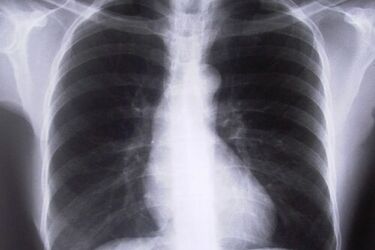

Badania i konsultacje odbywają się w ramach programu "Chwytaj każdy oddech". Jego celem jest edukacja pacjentów w zakresie chorób płuc ze szczególnym uwzględnieniem profilaktyki, roli wczesnej diagnostyki i leczenia astmy i POChP.

Pacjenci w całej Polsce będą mogli wykonać bezpłatnie badanie spirometryczne, a w razie potrzeby także skorzystać z porady lekarza specjalisty, który dokona analizy wyniku badania. Program swoim autorytetem wsparli wybitni eksperci w dziedzinie chorób płuc.